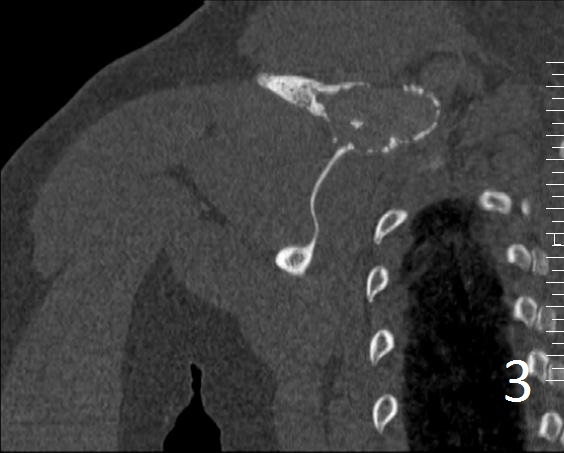

• Useful to determine the extent of the lesion as well as ground glass appearance (Fig. 2-3)

• Well defined borders

• Possible endosteal scalloping lesion

• Areas of mineralization within.

Fig. 3. Coronal CT of the right shoulder shows a expansile lytic lesion with cortical bone expansion.